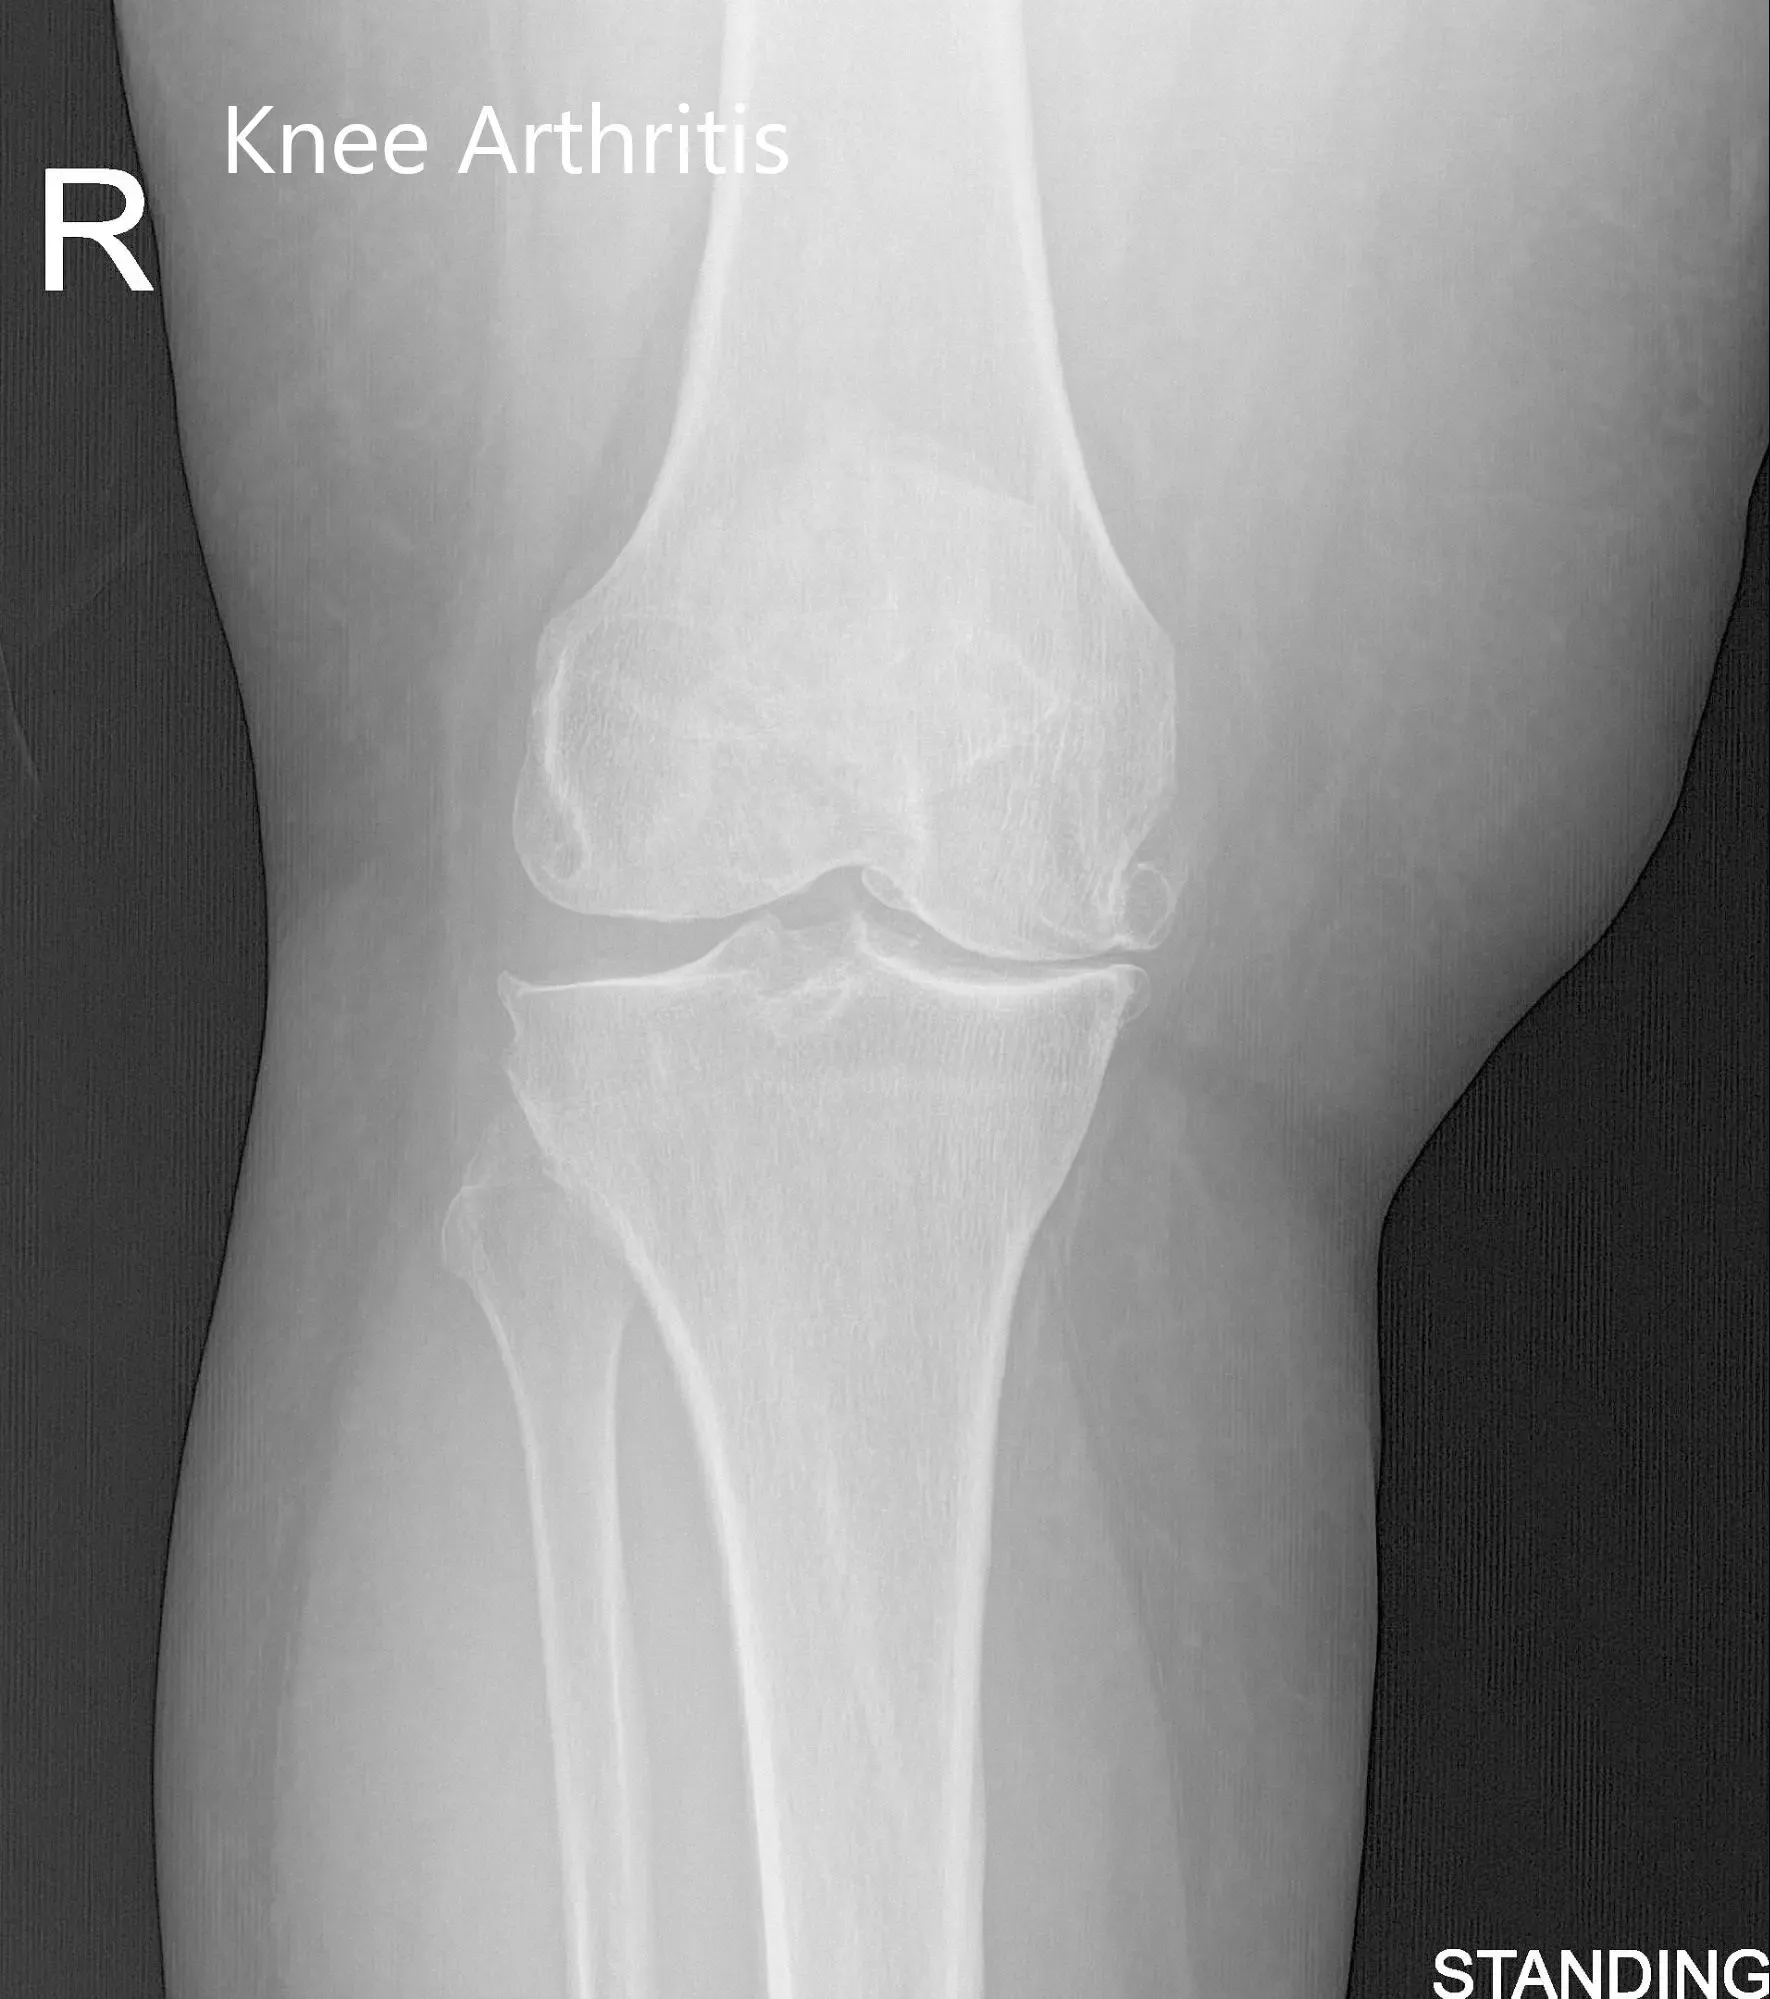

El examen físico reveló una deformidad genu-varo y una ligera inflamación en la articulación de la rodilla derecha. Hubo una crepitación articular marcada en todo el rango de movimiento con sensibilidad moderada en las líneas articulares medial y lateral y sensibilidad en las facetas rotulianas. Los estudios de imagen revelaron un estrechamiento marcado del compartimento articular medial y del compartimento articular patelofemoral con formación moderada de osteófitos.

Vistas preoperatorias de la rodilla derecha (de pie)